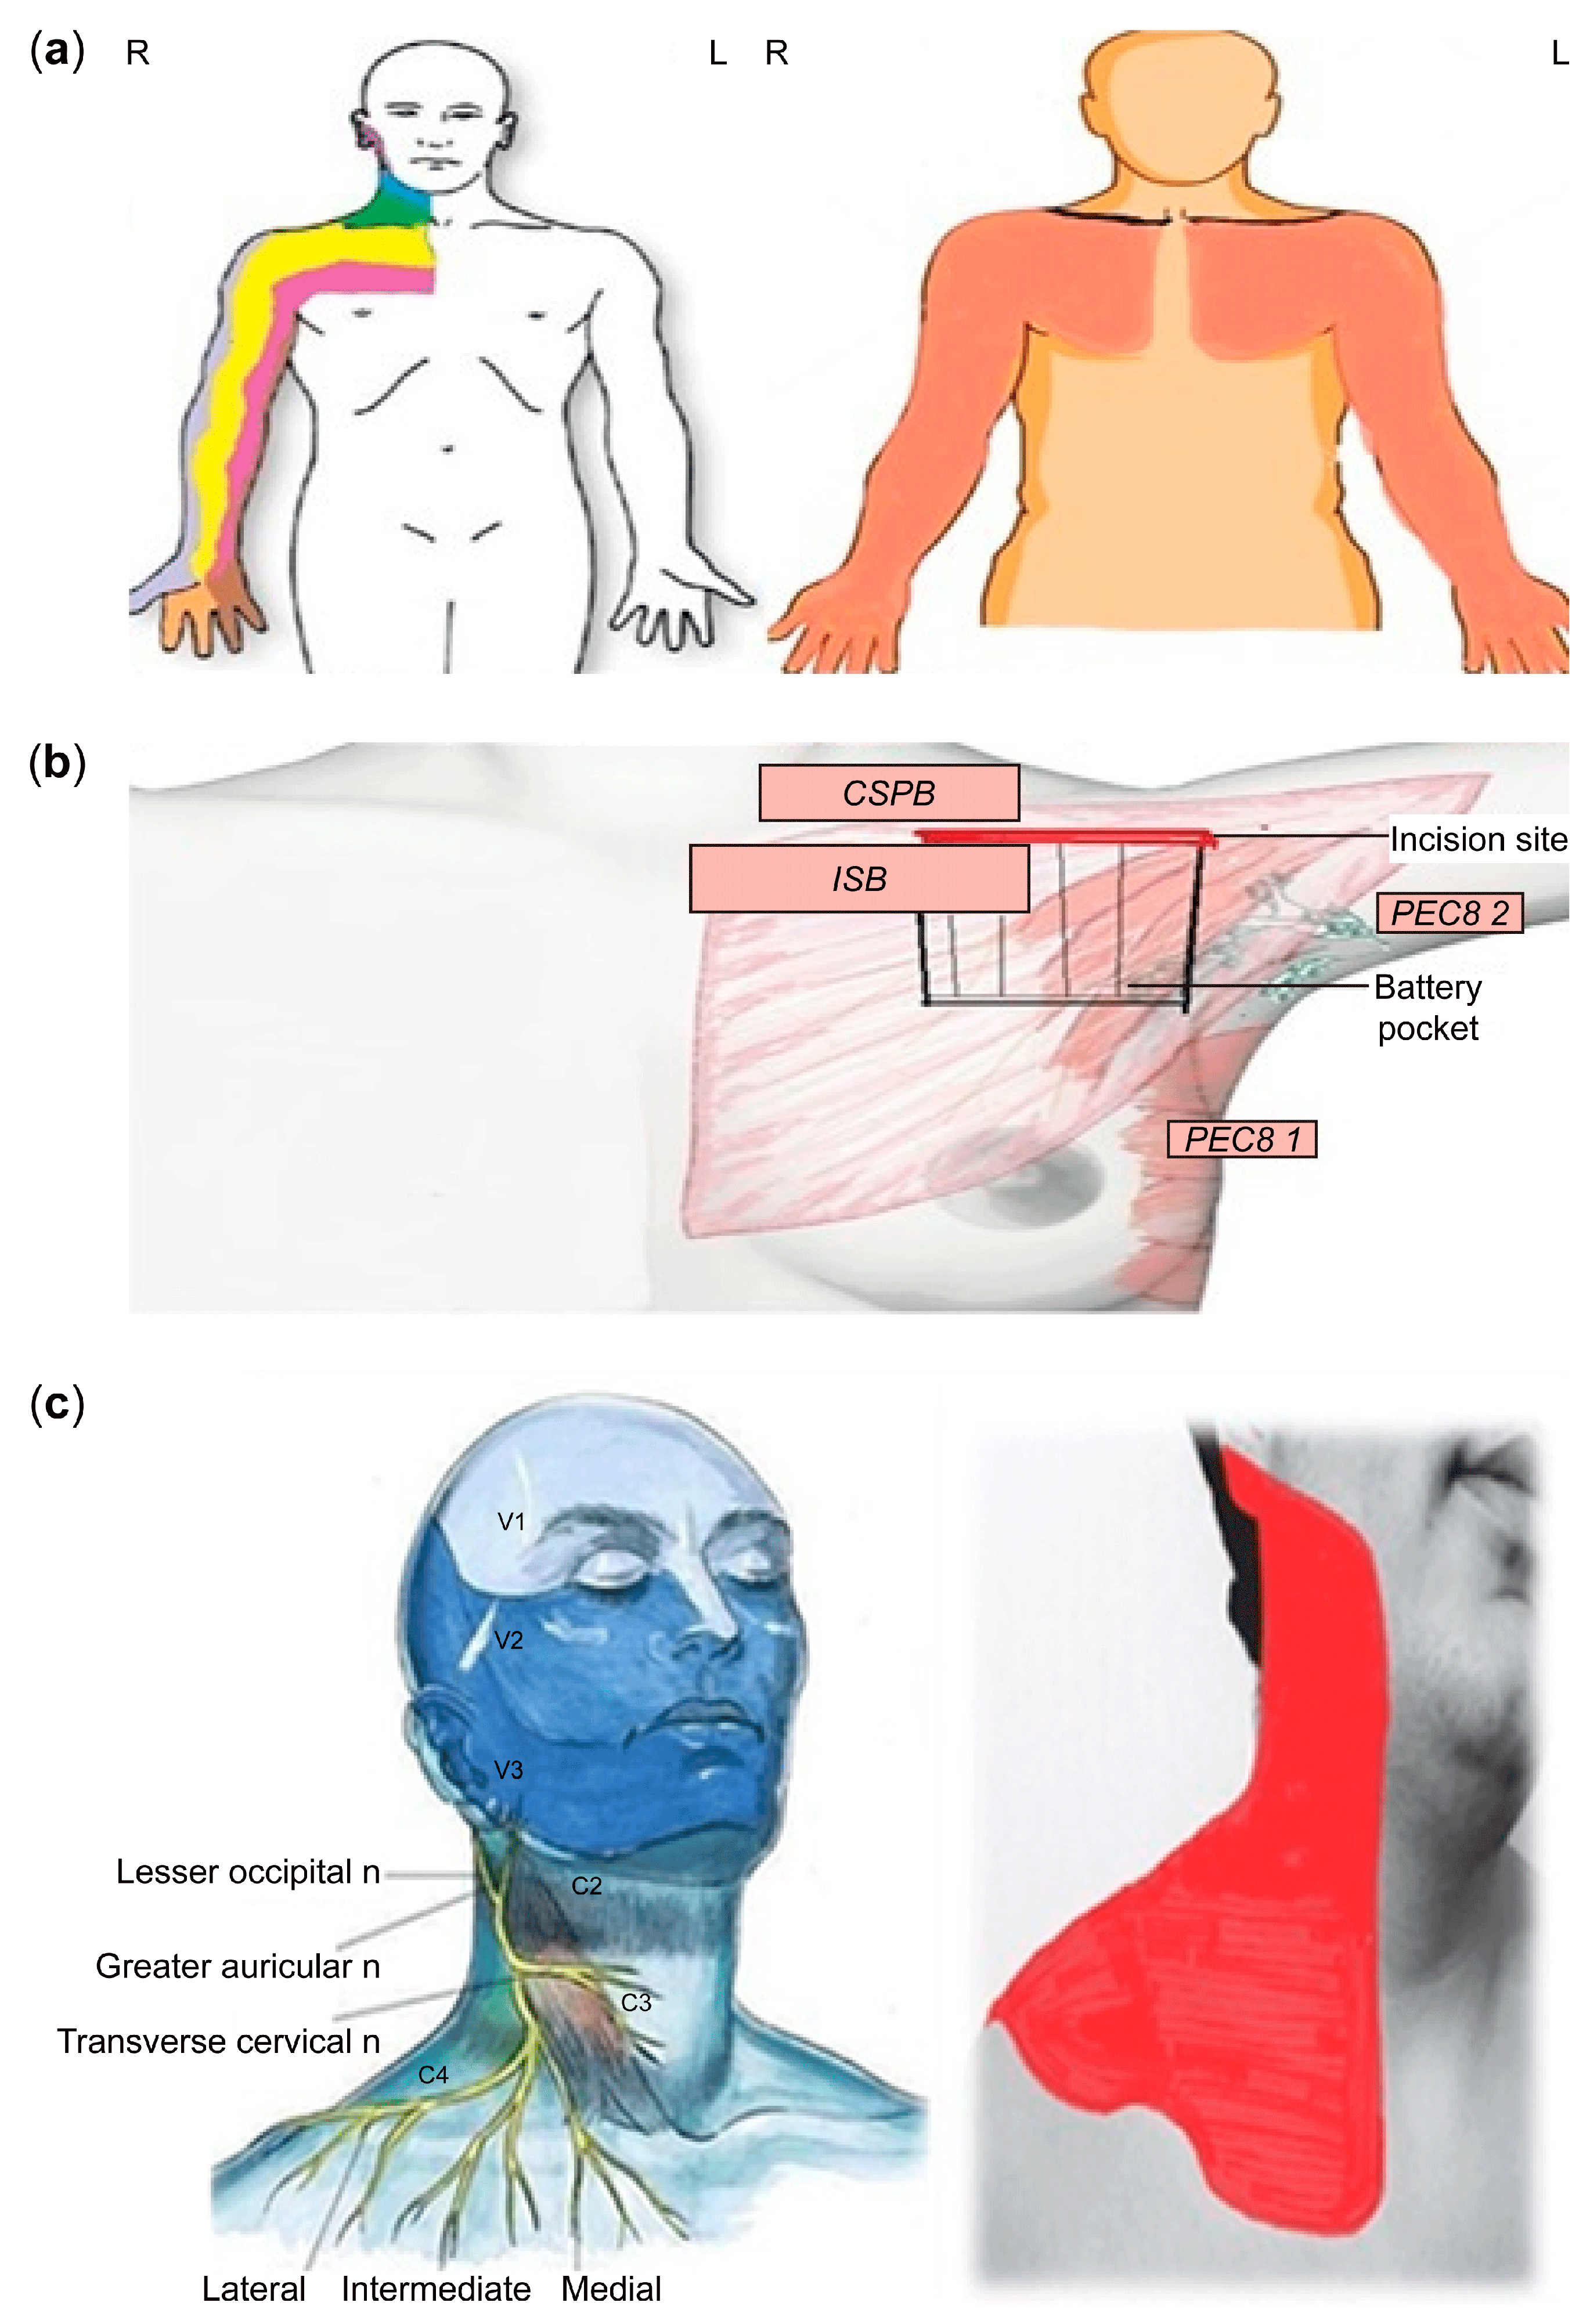

4. Anesthesia Preparation

4.1. Fluoroscopic-Guided Vascular Puncture in Posterior–Anterior (PA) Projection